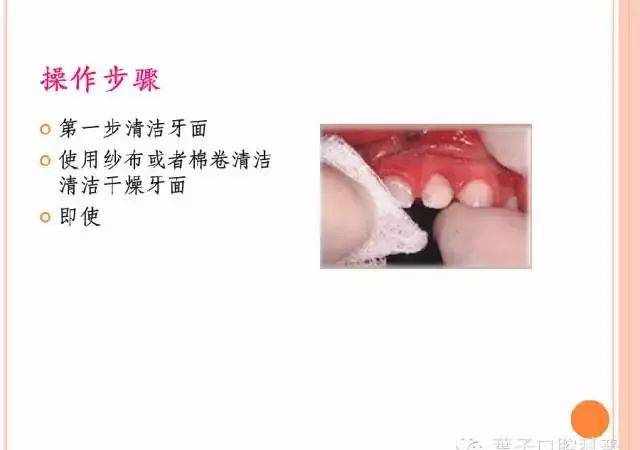

1.清洁牙面

2.把牙面冲洗干净,干燥牙面